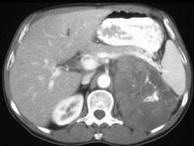

问题 女,43岁,满月脸、皮肤紫纹、月经不规则3月余,请结合所提供图像,作出诊断()

选项 A.左肾上腺腺瘤 B.左肾上腺嗜铬细胞瘤 C.左肾上腺转移瘤 D.左肾上腺腺癌 E.左肾上腺增生

答案 D